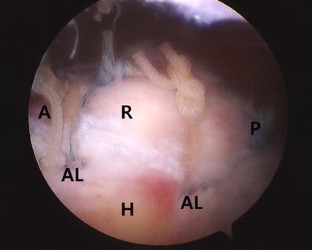

Fig. 1

Fig. 2